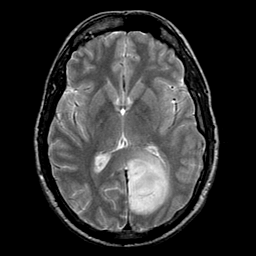

glioma overlay -- Slice #14

[Home][Help][Clinical] Slice 14